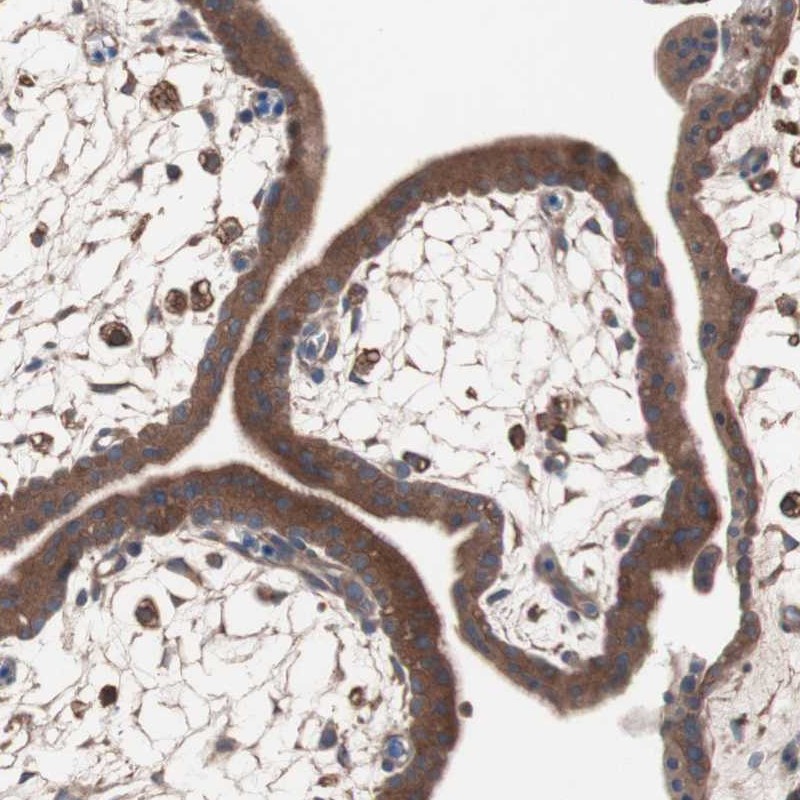

Immunohistochemical staining of human placenta shows moderate cytoplasmic positivity in trophoblastic cells.